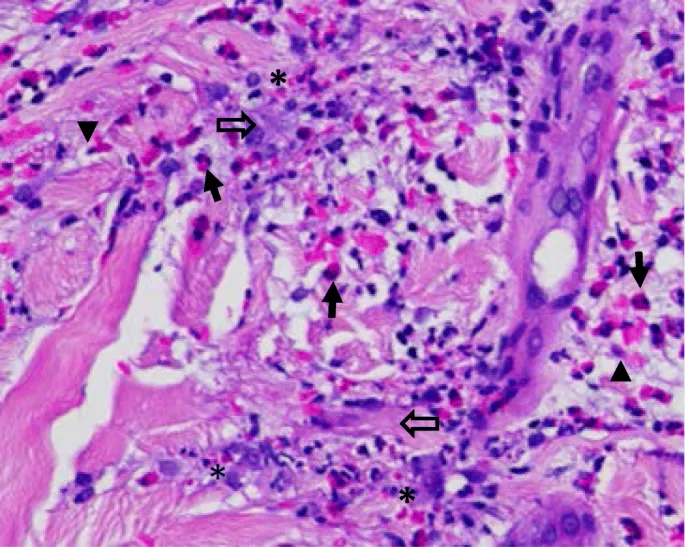

| Biopsy findings | Amastigotes | Neutrophilic infiltrate | Chronic inflammation | Malignant cells | Pathognomonic |